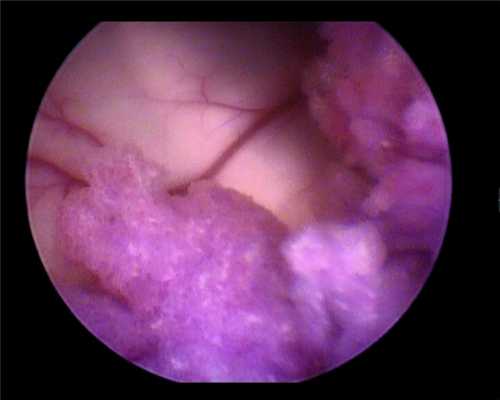

Данные нейросонографии изменили хирургическую тактику — доступ к опухоли был осуществлен транскортикально через теменную долю к области желудочкового треугольника с кортикотомией до 1 см. На глубине 2 см вскрылся правый боковой желудочек, в рану под давлением стал поступать ликвор, в правом боковом желудочке обнаружилось новообразование розового цвета, по виду типичная хориоидпапиллома (рис. 3).

Рисунок 3. ПСС — момент осмотра патологического образования и анатомических структур, прилежащих к нему. Эндоскоп 30°. Удаление образования начато с помощью биполярной коагуляции, отсоса и микроножниц.